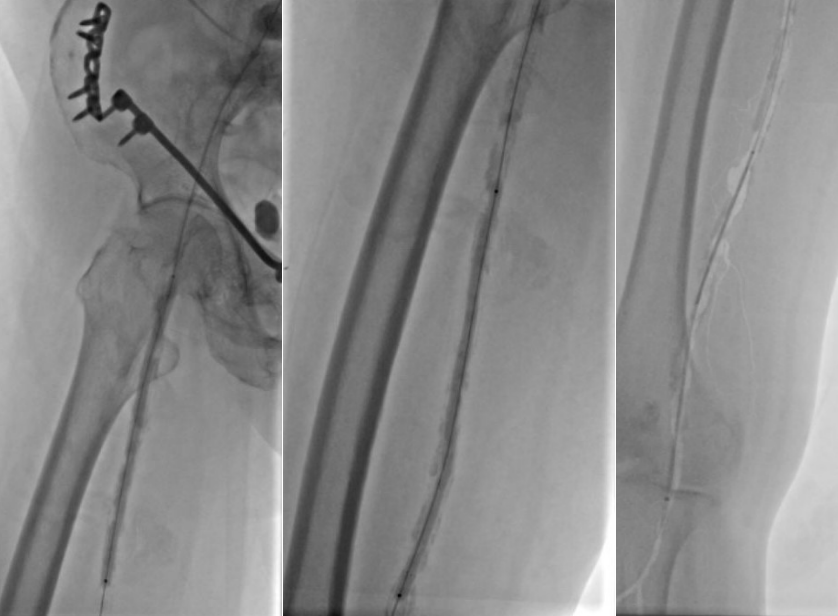

1. 术前造影:

2. 经鞘置入椎管、CXI、V18导丝正向开通股浅动脉下段,导丝通过,导管无法跟进,经皮穿刺钙化灶,导管跟进造影发现位于内膜下。

3. 经皮穿刺胫前动脉上段,置入新V18导丝,跟进CXI,与正向的椎管双向会师,建立导丝通路,予以3.0球囊预扩张。